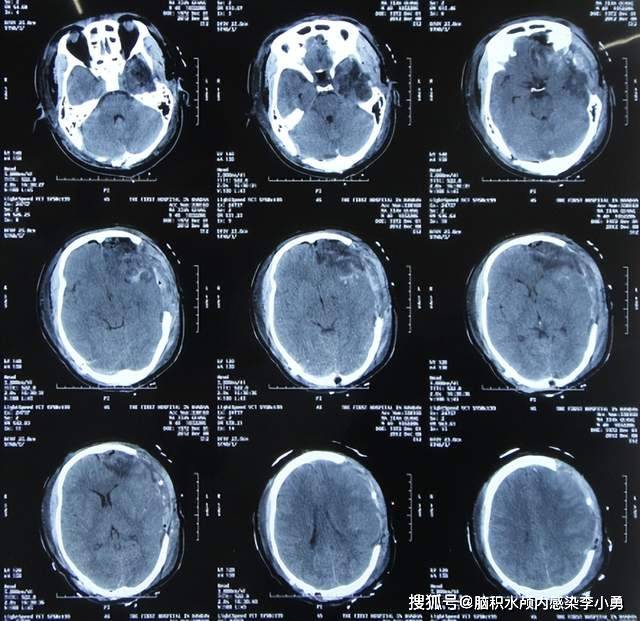

期间4次查头颅ct(图-21,图-22,图-23,图-24)均示脑积水未缓解,且多次

图-18:2020年4月10日头颅ct图-17:2020年4月2日头颅ct第二家医院继续